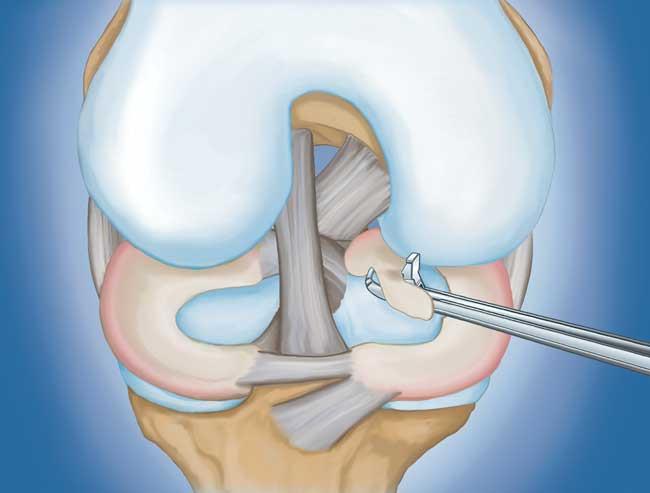

程序。 膝關(guān)節(jié)鏡檢查是最常進行的外科手術(shù)之一。在這個過程中,外科醫(yī)生通過膝蓋上的一個小切口(入口)插入一個微型相機。這提供了膝蓋內(nèi)部的清晰視圖。然后外科醫(yī)生通過兩個或三個其他小入口插入手術(shù)器械以修剪或修復(fù)撕裂。

- 部分半月板切除術(shù)。 在這個過程中,受損的半月板組織被修剪掉。該程序通常允許在手術(shù)后立即負重和全方位運動。

在這段簡短的手術(shù)視頻中,半月板部分切除術(shù)期間使用電動剃須刀平滑了退行性半月板撕裂。

- 半月板修復(fù)。 一些半月板撕裂可以通過將撕裂的碎片縫合(縫合)在一起來修復(fù)。撕裂能否成功修復(fù)取決于撕裂的類型,以及受傷半月板的整體狀況。因為半月板必須一起愈合,修復(fù)的恢復(fù)時間比半月板切除術(shù)長。